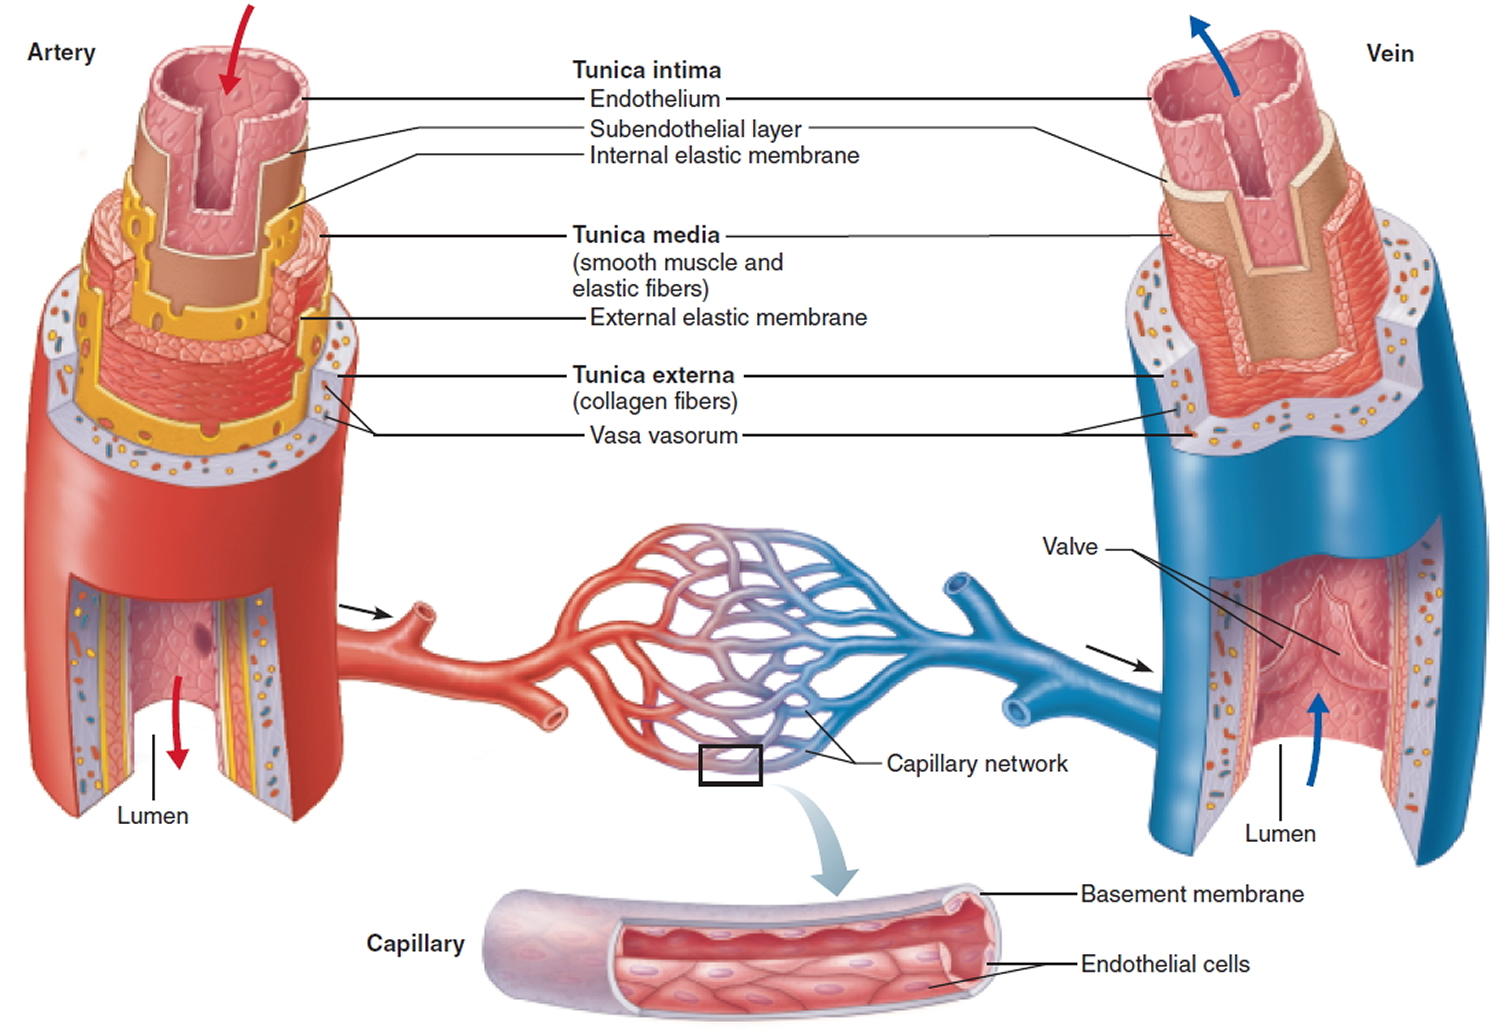

All blood vessels have one or ore layers around them depending on the type of of vessel, artery, arteriole, capillary, venue, or vein.

As you can see, there are considerable differences in the number and thickness of these layers. As usual structure is related to function. Arteries have to withstand the highest pressures as the heart contracts and forces blood into the system. that why you found elastic connective tissue in the walls of the aorta back in histology. Capillaries have a single, simple squamous layer to allow maximum diffusion of materials into or out of the vessel.

Veins have the lowest pressure and need valves to ensure blood flows in the correct direction in the vessel (just like lymphatic vessel). As you can see from the graph, blood pressure and velocity drop rapidly as it enters the capillaries because the total vessel volume rapidly increases.This provides maximum time for exchange of materials between vessels and cells.